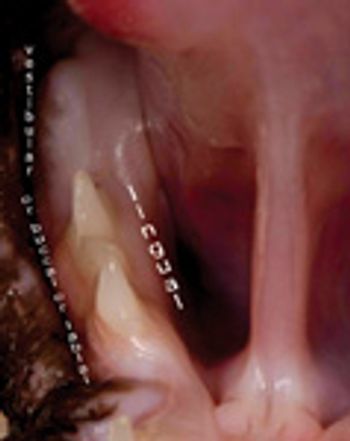

Mandibular fracture is a relatively common injury. Surgical repair of the mandible is complicated by the presence of tooth roots and a mandibular canal with its neurovascular contents.